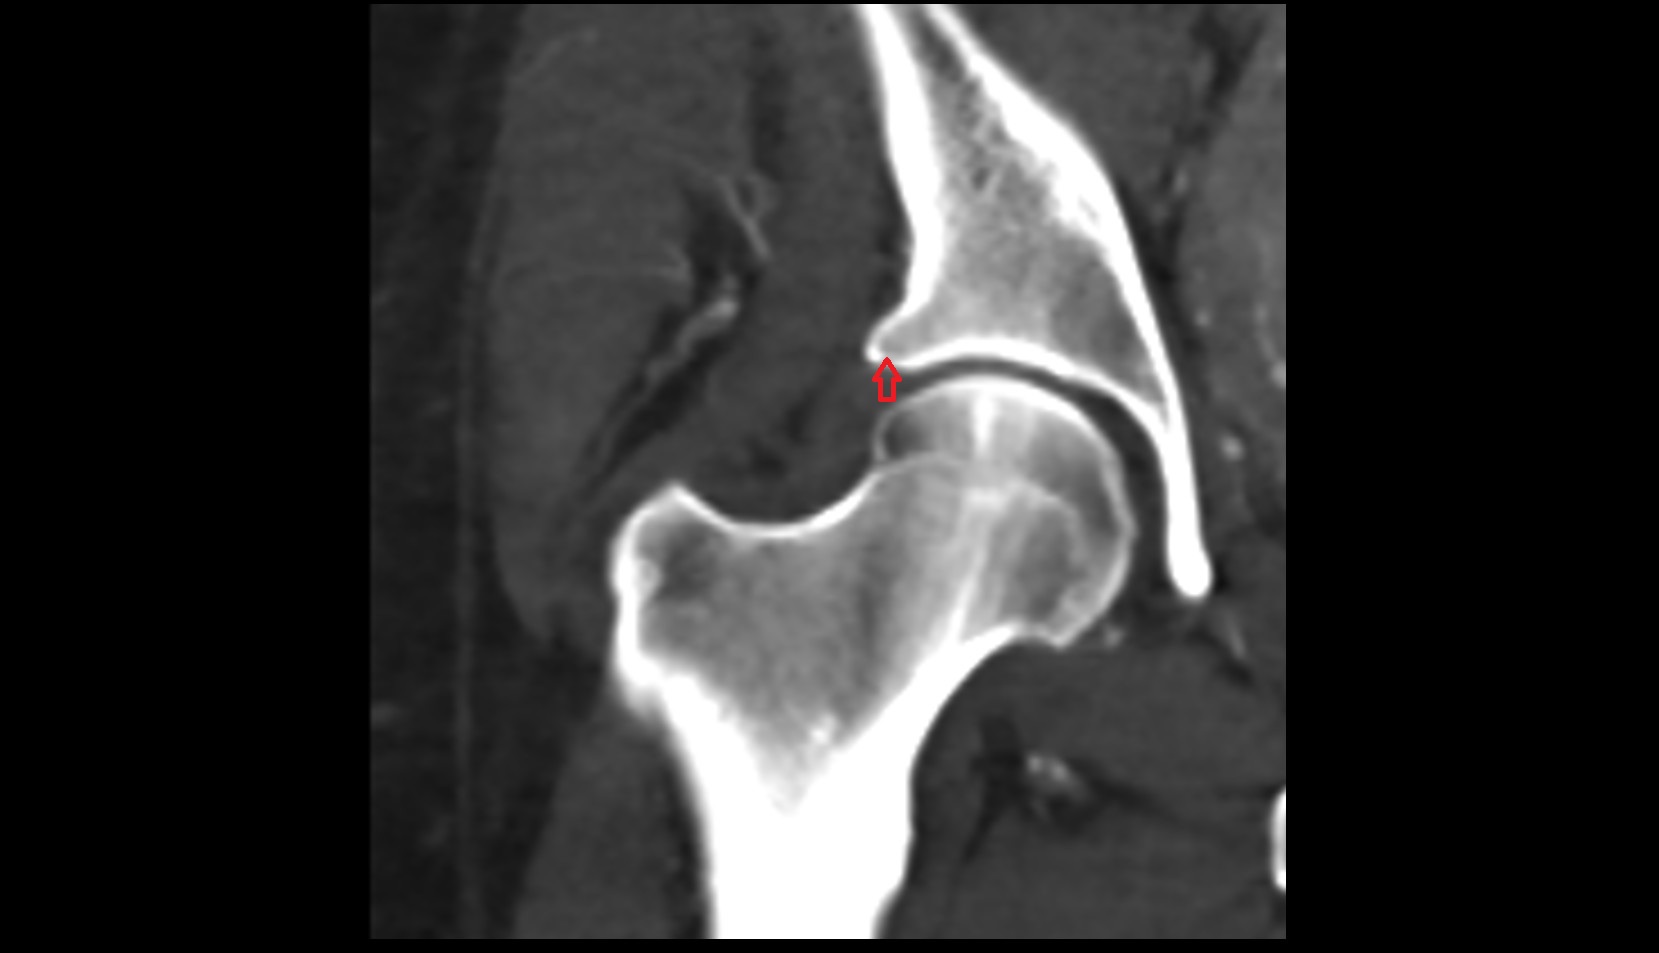

- Head of femur

- Neck of femur

- Acetabular labrum

- Articular capsule of hip joint

- Hip joint